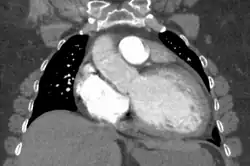

Dilated cardiomyopathy on CT

Generalized enlargement of the heart is seen upon normal chest X-ray. Pleural effusion may also be noticed, which is due to pulmonary venous hypertension.[28]